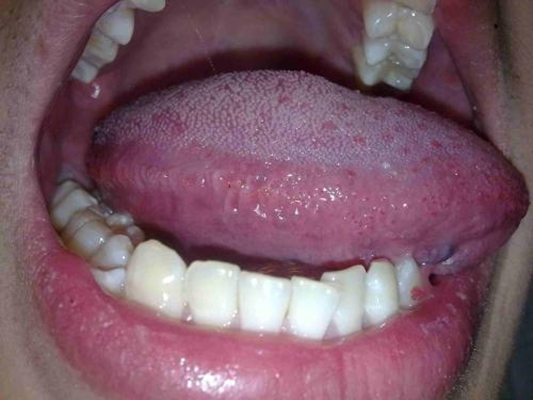

口腔黏膜病圖片

口腔念珠菌感染 (48)